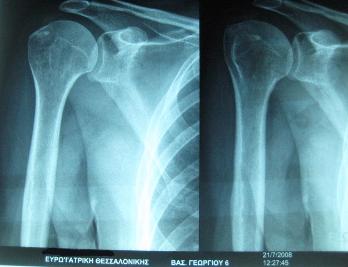

Επασβέστωση πριν και μετά από 6 θεραπείες σε ενήλικα γυναίκα. Η ασθενής δεν χρειάστηκε να σταματήσει την εργασία της. |